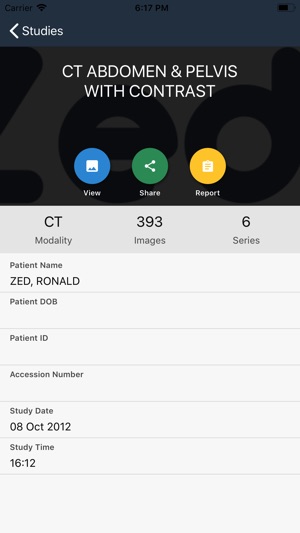

Zed Doctor is an app for viewing medical imaging studies. Please contact us at support@zedtechnologies.com.au for your free account.

The viewer displays selected studies and reports via an intuitive user interface and allows key images and associated reports to be forwarded to other referrers involved in patient management.